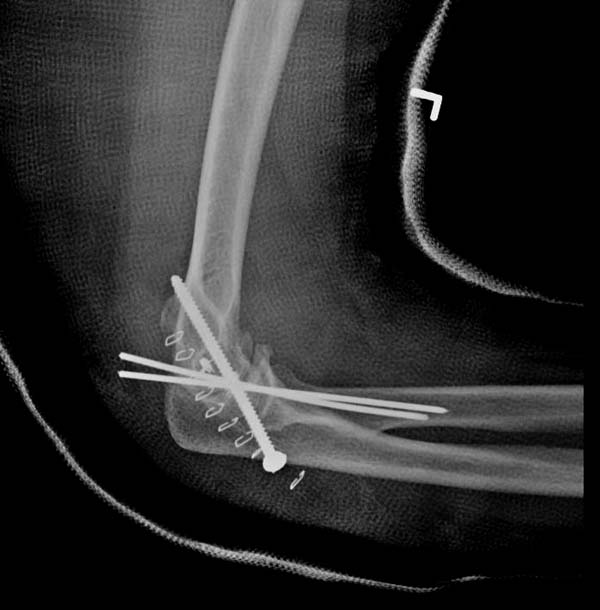

Снимки: 1-2 вывих, 4-5 вторичное смещение в гипсе, реконструкция

латеральной связки и капсулы 13-14, повторный вывих после реконструкции,

перевод в наш центр; 18-21 временная фиксация, 22-25 трансартикулярная

фиксация и нестабильная головка фиксирована спицами, 29-30 амбулаторно,

Имя     : 22 Elbow dislocation closed reduction SLU 7.JPG

Тип     : image/jpeg

Размер  : 28223 байтов

Описание: отсутствует

Url     : http://weborto.net:8080/pipermail/ortho/attachments/20131212/4b05a6a3/attachment-0010.jpeg